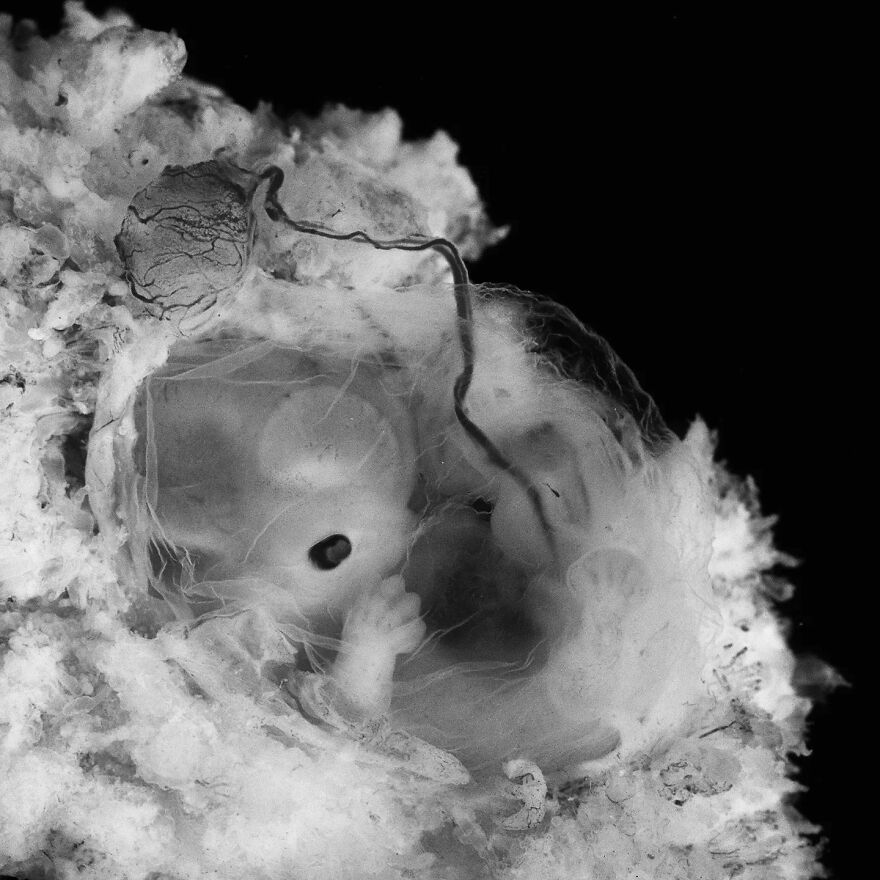

Fetus, 11-12 weeks

About 8 weeks? Just mentally comparing with our son's sonogram. Obv due to the different technology, that's not easy nor fool-proof.